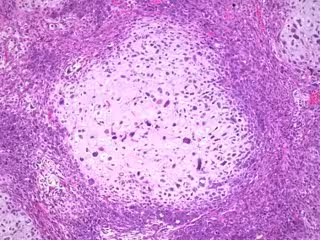

Estos estudios utilizaron líneas celulares de cáncer de seno ER + que están disponibles comercialmente, así como tejidos tomados de pacientes con cáncer de mama incluidos aquellos resistentes a las terapias actuales. Se cultivaron algunas líneas celulares y tejidos humanos en placas de cultivo, y otras líneas celulares y tumores de pacientes se transplantaron a ratones para crear modelos derivados de pacientes.

En todos los modelos, los investigadores encontraron evidencia de que la actividad estimulante del receptor de andrógenos con enobosarm detuvo el crecimiento tumoral. De los diferentes modelos de cáncer de mama, derivaron una firma genética de la actividad del receptor de andrógenos, que predijo la supervivencia del cáncer en participantes en grandes estudios de cáncer de mama ER +. Esta firma del receptor de andrógenos superó a otras firmas de pronóstico de cáncer de mama, asegura.